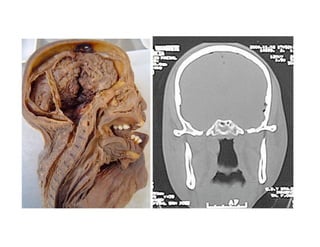

Este documento describe los principios de construcción de la arquitectura craneofacial, incluyendo el metamerismo, la simetría y la paquimería. Explica la organización peri-cavitaria del cráneo a través de columnas y vigas, y analiza las diferentes fascias profundas del cuello. También destaca la importancia de conocer la irrigación ósea con orientación quirúrgica, mencionando los principales aportes vasculares y suplementarios así como el origen, trayecto y retorno venoso de la carót